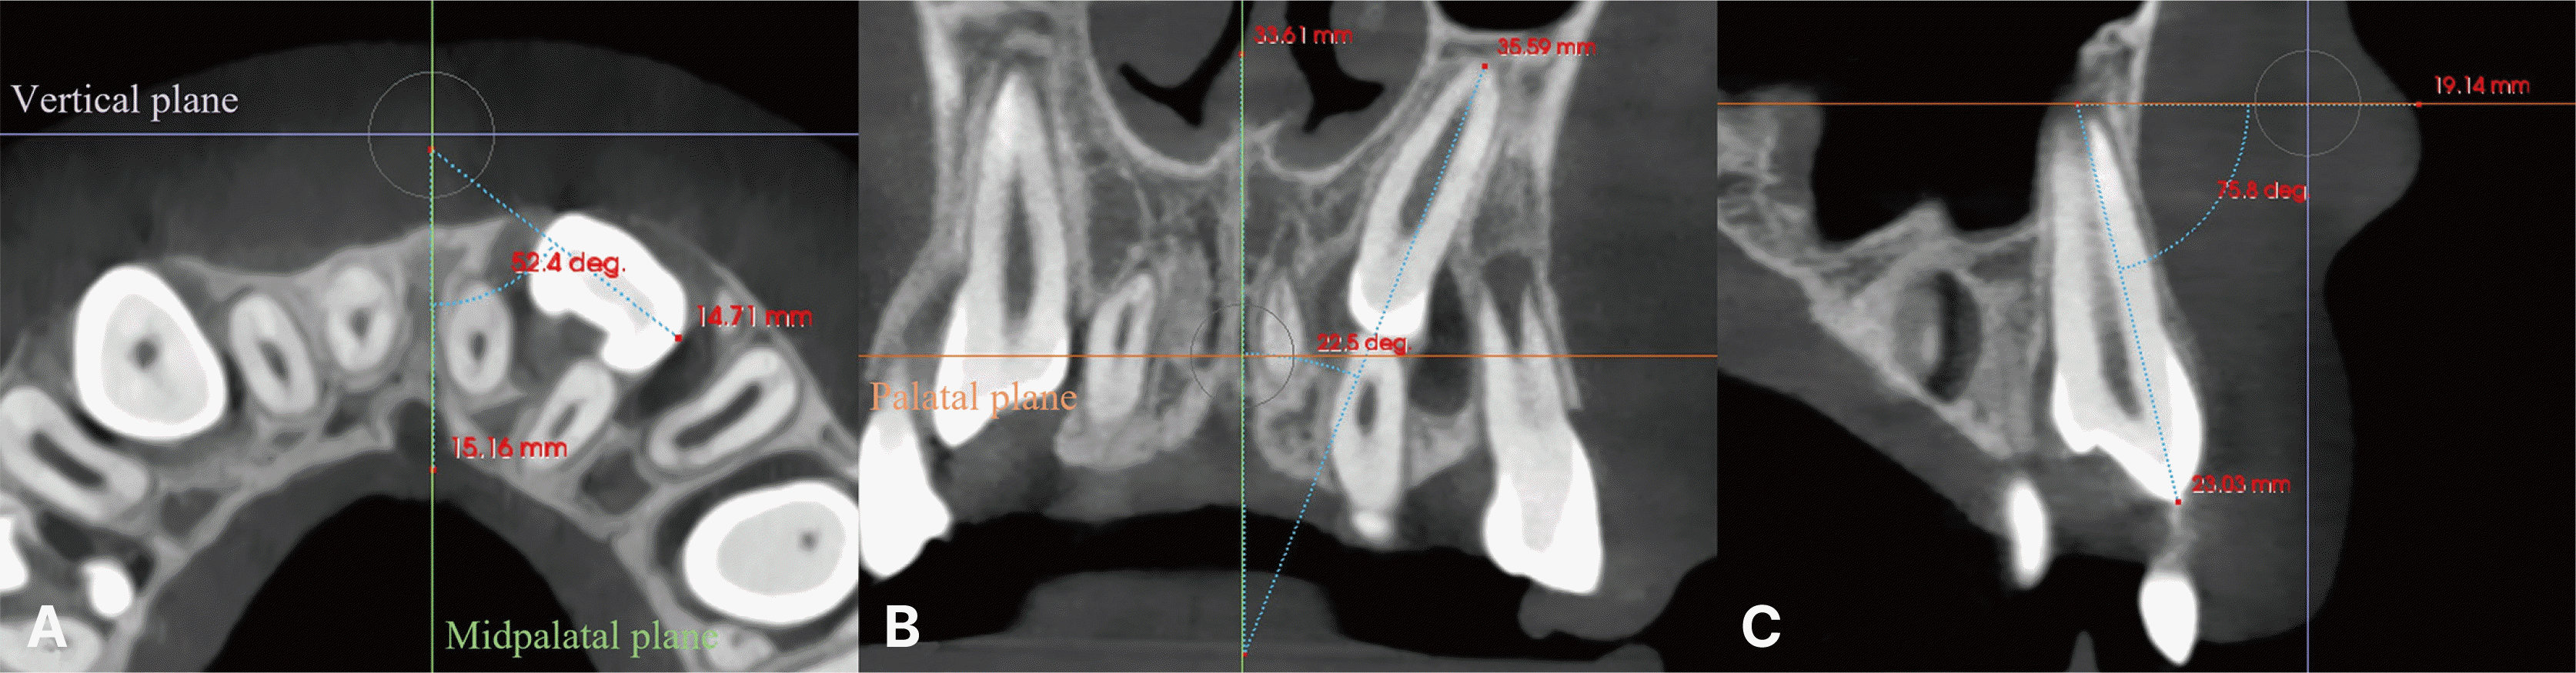

The CBCT images in this study were analyzed using Invivo 6 plus, version 6.5 software (Anatomage, San Jose, USA) by a single investigator (J.E.J). Variables such as rotation, angulation, torque, root volumes, root lengths, and the presence of hooked apices were measured. The palatal plane, defined by the horizontal line connecting both orbitales and passing through the ANS and PNS, served as the horizontal reference. The midpalatal plane, passing through the ANS and PNS and perpendicular to the palatal plane, was used as the vertical reference. A vertical plane through the ANS and perpendicular to both the palatal and midpalatal planes functioned as the transversal reference (Fig. 1).

Rotation was quantified in the axial view as the angle between a tangent to the buccal contour of the tooth and the midpalatal plane. Inclination was determined in the coronal view as the angle between the tooth’s long axis and the midpalatal plane. Torque was evaluated from the sagittal view as the angle between the tooth’s long axis and the palatal plane (Fig. 2). Further, the canine’s root length, root volume, and the presence or absence of an apical hook were assessed. Root length was measured along the long axis from the canine tip to the root apex using a three-dimensional model of canine segmentation. Root volume was calculated from the volume of the entire tooth (including the crown) using a three-dimensional model of canine segmentation. An apical hook was considered present if the angulation in the apical third of the canine root exceeded 50 degrees relative to the root’s long axis (Fig. 3).